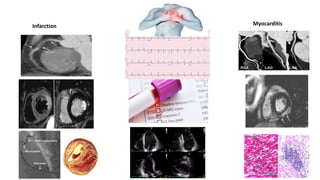

Myocarditis

Infarction

• #12 This is the slide that I have prepared myself to improve your better in differenciating myocardial infarction or ischemia from myocarditis which is crucial to recognize in order to guide correct and optimum management strategy. This has to be adopted right in the beginning . Every assessment in Medicine begins with the basics. In other words to very well understand the initial clinical presentation. You will see here three vertical panels where I have tried to demonstrate the features of infarction on your left and myocarditis on your right. The middle panel is common to both. History of chest pain , ECG changes and rise in Troponin sometimes may not help and may be inadequate to differentiate between the two. Echo cardiogram would show regional wall motion abnormalities in MI and global LV dysfuction in myocarditis . Other imaging modality is cardiac MRI ( mid wall or epicardial LGE in myocarditis while endocardial LGE in iscahema or infarction ) . However, the definitive investigation would be CAG in CAD while it will be EMB in myocarditis , both of which are difficult to obtain very sick COVID patients. To meet this leverage , CT coronary angiogram can be helpful. Will show obstruction of Cas in CAD while they are clear or non obstructive in myocarditis.